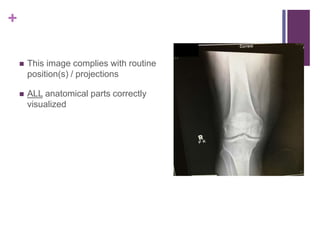

 This image complies with routine

position(s) / projections

 ALL anatomical parts correctly

visualized